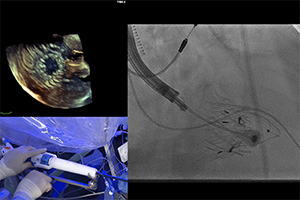

Vol 14, No 2 (March 31, 2025): TAVR Explant